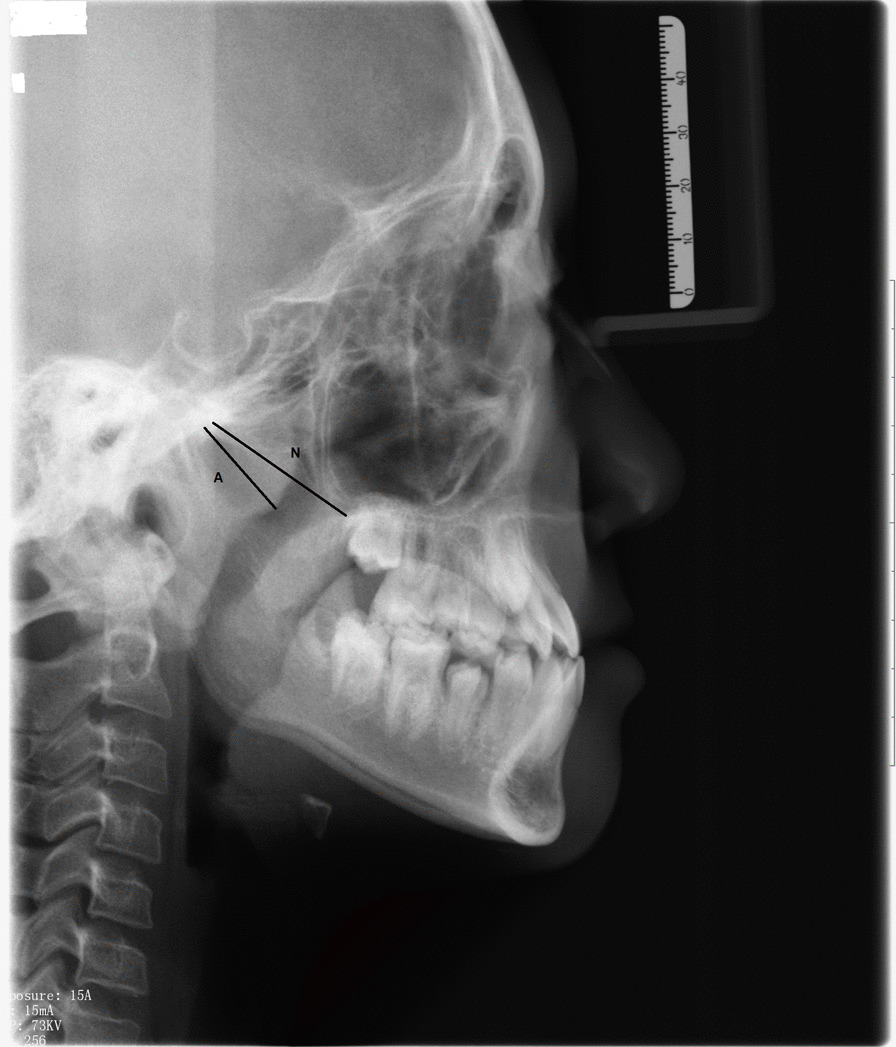

The AN ratios were measured and calculated on the lateral cephalograms captured by a digital pan/ceph system (ORTHOPHOS XG 5; Sirona Dental Systems, Bensheim, Germany) at 73 kVp and 15 mA with exposure times of 9.4 s and a contrast resolution of 16-bit depth. A is defined as a perpendicular distance between the point of maximal convexity of the adenoid to the anterior margin of the basiocciput. N is the distance between the posterosuperior edge of the hard palate and the anteroinferior edge of the spheno-occipital synchondrosis [9] (Fig. 1).

Fig. 1.

Calculating the adenoidal nasopharyngeal (AN) ratio on a lateral cephalogram. A, Perpendicular distance between maximum convexity of the adenoid shadow and the anterior margin of the basiocciput. N, Distance between the posterosuperior edge of the hard palate and the anteroinferior edge of the spheno-occipital synchondrosis